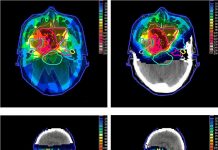

What Is Proton Therapy?

Por: Valter Aleixo.

Proton therapy or proton beam therapy is a type of particle therapy that uses a beam of protons to...